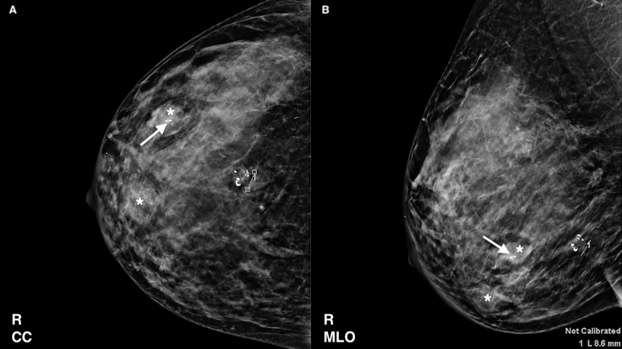

On mammography, fibroadenomas are typically well-circumscribed, round, oval or lobulated masses of varying sizes.1 They are often associated with so-called “popcorn calcifications”, which are coarse calcifications seen in involuting or hyalinizing fibroadenomas. When present, the diagnosis of a benign fibroadenoma can be made with certainty.1,4